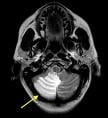

“The Society of Interventional Radiology has assembled a large group of stroke experts to teach the medical management of stroke patients, cerebral imaging, interventional techniques of revascularization and the stroke team concept,” said Carl M. Black, M.D., an interventional radiologist/neuroradiologist at Utah Valley Regional Medical Center in Provo. Many topics will be covered including the pathophysiology of ischemic stroke, neurological examination/NIH stroke scale, extensive aspects of neuroimaging, screening for stroke, stroke risk factor management, patient selection (imaging criteria), drugs used in interventional therapy, the nuts and bolts of setting up a stroke center and the role and timing of rehabilitation, said Black.

After completing the course, attendees should be able to describe the recent developments in acute stroke therapy and interventions, discuss essential elements of multidisciplinary stroke team development, analyze imaging modalities used in evaluation of acute ischemic stroke, describe intra-arterial techniques for treatment of acute ischemic stroke and demonstrate knowledge of guide catheters, microcatheters, pharmaceuticals and infusion systems. Participants will review teaching cases that will be posted on the SIR Web site, and attendees will have the opportunity to take written and practical exams on completion of this course to assess knowledge of basic principles that were covered.